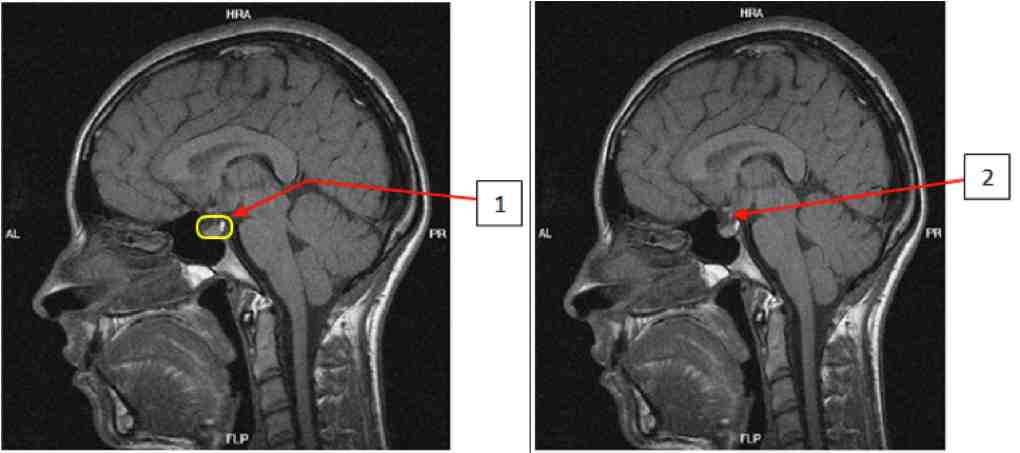

Document 2 : IRM de l'hypophyse http://www.chups.jussieu.fr

IRM de référence

IRM de Madame A

Ce type d'adénome est une tumeur bénigne provoquant une modification de l'activité des cellules sécrétant la prolactine, à l'origine de l'augmentation de taille de la glande.